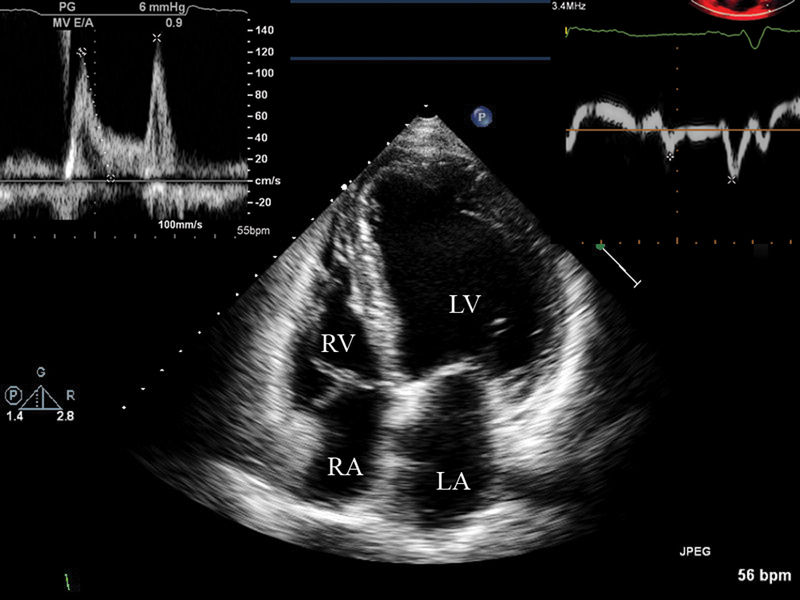

فحوصات تشخيصية لبعض امراض القلب والشرايين التاجية